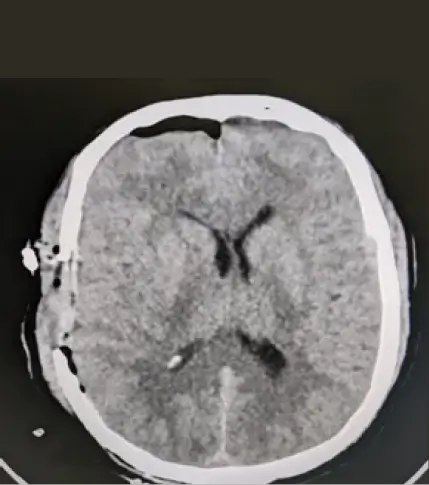

CT scan showed a huge extradural clot (150ml). Emergency craniotomy was performed within 20 minutes. Clot was extracted and bleeding was controlled. He gained consciousness and responded to verbal commands. His GCS improved and discharged home. However, he needs rehabilitation for at least 6 months to gain muscle strength, walking capability, regained bladder control.

EDH Before Craniotomy